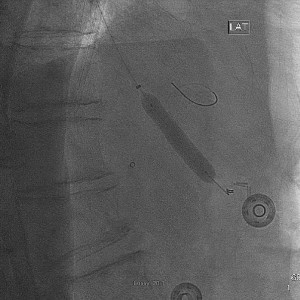

The celiac artery was engaged with a 5F Cobra-1 guide catheter and a 0.014 inch hydrophilic coronary wire was used to cross the lesion (Fig 1).

Crossing a severe stenosis of the celiac trunk from the femoral approach. Note the unfavorable angle of the guide catheter with the target vessel and the ostial location of the lesion.